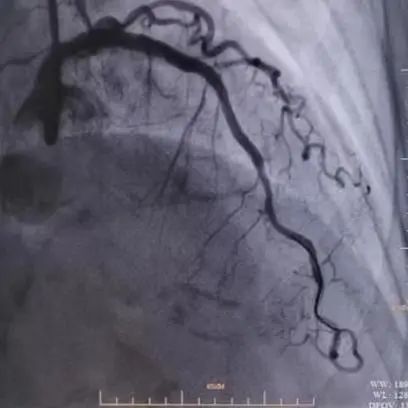

入院后冠脉造影提示:左主干体部狭窄约20%,前降支近段至中段血管迂曲,局部可见明显成角伴钙化,最重处狭窄80%。回旋支细小,管腔未见明显狭窄。右冠全程弥漫性粥样硬化伴钙化,近段狭窄约40-50%,远段狭窄约60%,左室后支开口狭窄50%。

在6F EBU 3.5指引导管到位左冠后,沿前降支导丝送血管内超声(IVUS)导管无法通过病变,遂先予Sprinter 2.5×15mm球囊8atm扩张前降支病变,造影可见球囊膨胀呈“狗骨头现象”。球扩后再次送IVUS导管成功通过病变检查提示:病变处弥漫性纤维钙化斑块,局部可见180-330°钙化环,钙化厚度约0.2mm-0.4mm,长度约8mm,局部可见钙化小结。

图2.病变处理前/普通球囊预处理中/冲击波球囊预处理中的冠脉造影图片对比